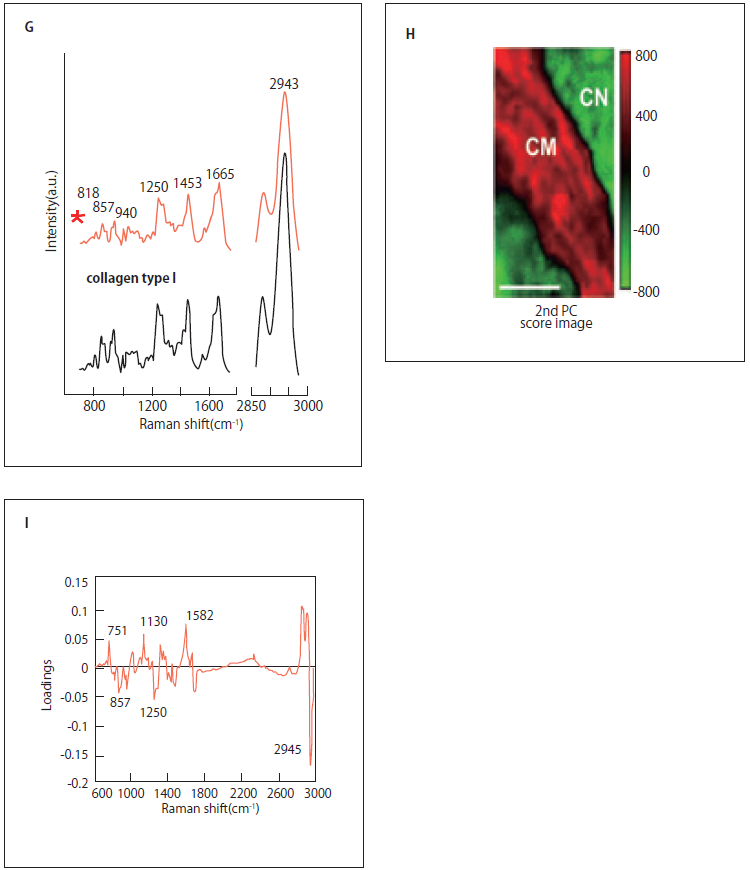

ラマン散乱光による心筋梗塞イメージング

光を物質に照射するとその一部は散乱される。散乱光の大半は入射光と同じ波長を示すが、一部は入射光と波長が異なる。この異なった波長の散乱光をラマン散乱と呼ぶが、波長のシフト量はその物質を構成する分子構造に固有であるため、測定されたラマンスペクトルを解析することにより構成分子の同定が可能である。すなわち、ラマン散乱分光は、生きた細胞・組織中に存在する分子の構造やその変化を非破壊・プローブなしで解析可能であり、in vivo診断に適した分光法といえる12)。しかし、ラマン散乱の散乱断面積は非常に小さいため、定点での解析に用いられることはあってもイメージングはほぼ不可能であったため、ラマン分光法は医学・生物学の領域であまり用いられてこなかった。

近年、光学技術の急速な発展により、生理的な環境下でかつ十分な速度でラマンイメージングを行えるシステムが登場してきており、ラマン分光法を生体機能解析に利用する道が拓けてきた13)。我々は、同時に多点の測定が可能なライン照明とパラレル検出技術を取り入れた高速ラマン散乱顕微鏡システムを用いている14)。つまり、532 nm励起によるチトクロームの共鳴ラマン散乱を利用し、主成分分析によるイメージ再構築を行うことにより、無標識でラット心臓(正常・陳旧性心筋梗塞巣)の生体組織診断が可能であることを示した(図3B-I)。この技術を用いて、我々はin vivo無標識生体組織診断を目指している。

図3 ラマン散乱光による心筋梗塞イメージング

A)ラマン散乱の模式図。物質に光を入射したとき、入射光は違う波長で散乱される光をラマン散乱光という。このラマン散乱光は分子固有の分子振動に依存するため、ラマン散乱光を分光することで、分子の同定、構造を推定することが可能。B)心筋細胞のラマンスペクトル。心筋細胞のラマンスペクトルは還元型b5及びc型チトクロームの寄与が大きい。C) HE染色による心筋梗塞の境界領域イメージ。D) 線維染色による心筋梗塞の境界領域イメージ。E)Cのボックス領域の拡大イメージ。F)白色光イメージ。G)Fの線維性の組織(星印)とI型コラーゲンのラマンスペクトルの比較。H)Eの領域についてラマンスペクトル測定後、主成分分析した時の第2主成分ラマンイメージ。I) 主成分分析を適用した時の第2主成分ローディングプロット。正のバンドは還元型b5及びc型チトクローム(751, 1130,1582 cm-1)及び脂質(2854 cm-1)に関連。負のバンドはI型コラーゲン(857, 1250, 2945 cm-1)に関連。スケールバーは50µm(C, D);20 µm(E, F, H)。CM、ラット心筋細胞。